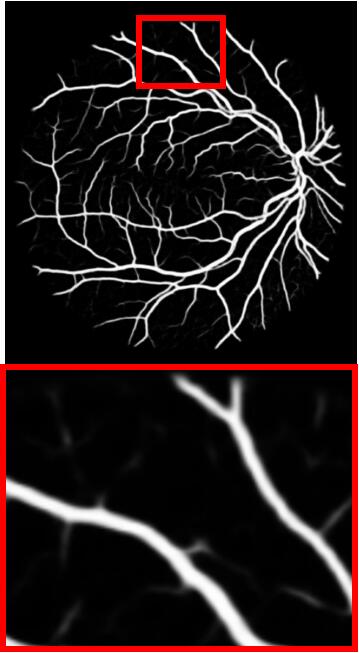

Refer to caption

(a) Input

(b) GT

(c) M-Net

(d) AG-Net

(e) BL

(f) BLST

(g) Ours

Figure 4: Example results for DRIVE. M-Net, AG-Net, and BL disregard some edge structures, which are very similar to textures. Conversely, by decomposing structures and textures, BLST gains better discrimination power and detects more tiny structures. Comparing (f) and (g), when adding the texture block, more tiny boundary structures are detected.

We remove the texture block, structure loss ssubscript𝑠{\mathcal{L}}_{s}, and texture loss tsubscript𝑡{\mathcal{L}}_{t} from STD-Net and name the baseline model as BL. The model BLST is formed by adding the structure-texture loss into BL. Fig. 4 shows a test example, including the ground truth vessel (GT) and segmentation results obtained by M-Net, AG-Net, BL, BLST, and the proposed STD-Net. The experimental results of BL and BLST are shown in Table 3.